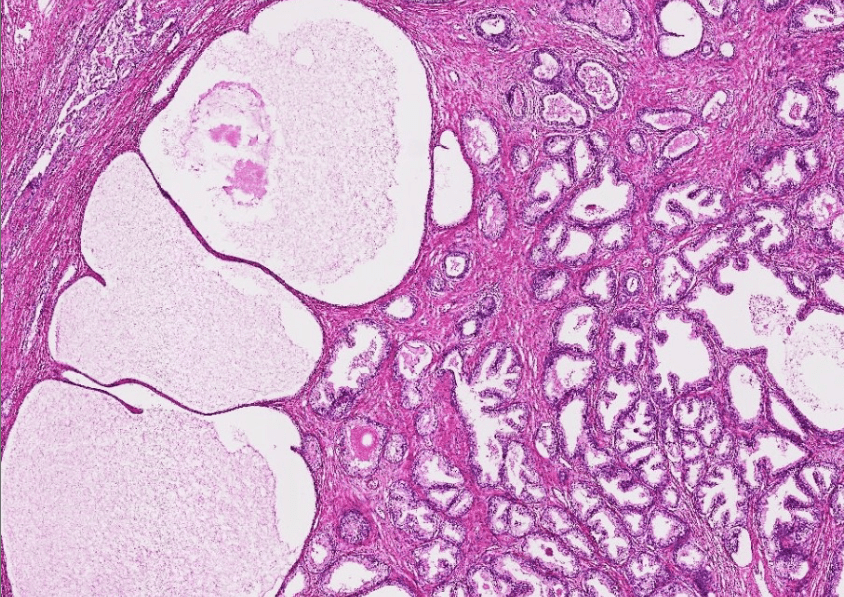

breast cancer